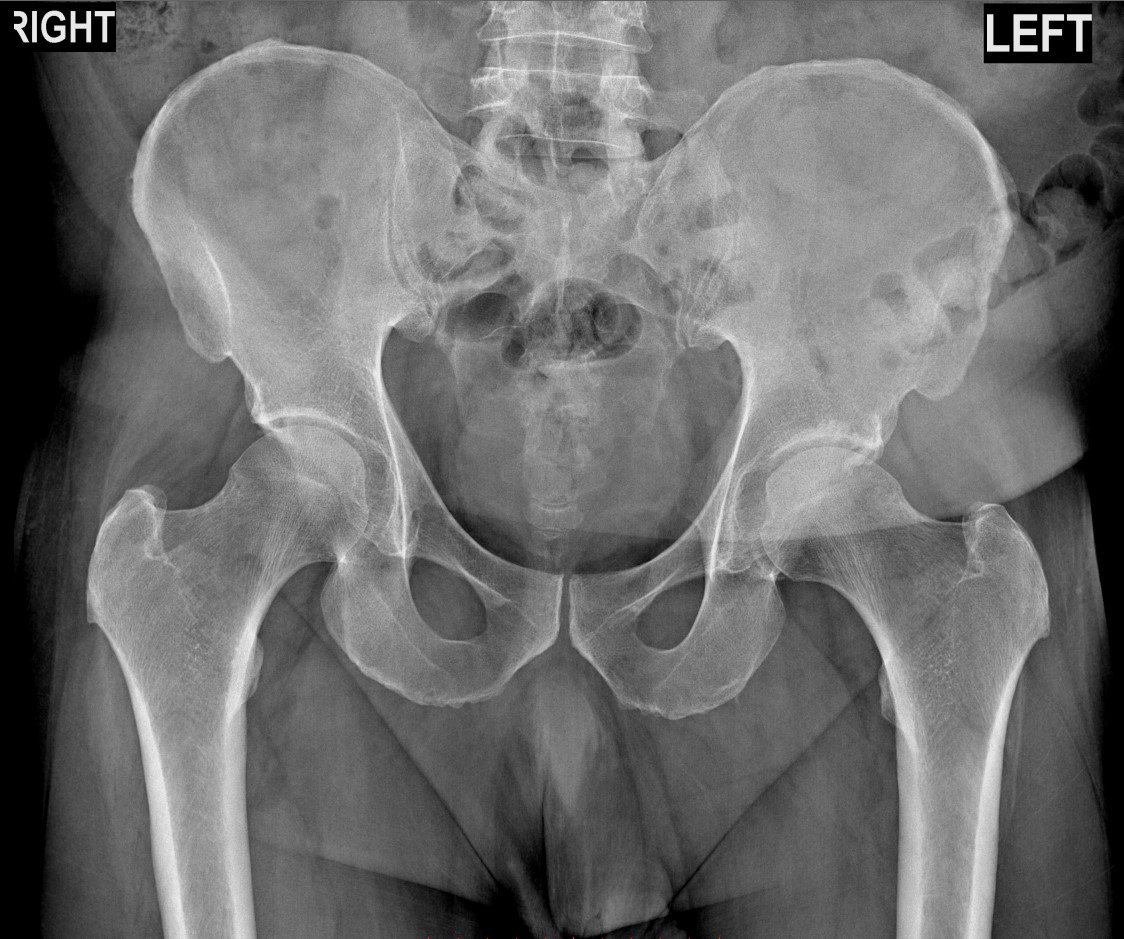

У второго пациента при осмотре был положителен тест FADIR (боль при сгибании, приведении и внутренней ротации бедра). Рентген подтвердил диагноз: импинджмент-синдром. Из-за выраженных дегенеративных изменений в тазобедренном суставе - шейка бедра «соударяется» с краем вертлужной впадины, вызывая боль и мышечно-тонический синдром.